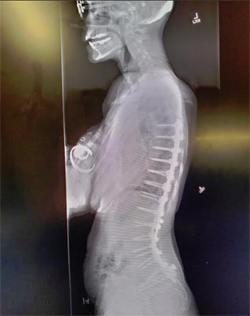

I was wearing a custom brace made of styrofoam and plastic. I wore it 24 hrs a day for a month then after just when I was up. I took it off after 2 months. This picture was taken at my first outing, 6 weeks after the surgery.